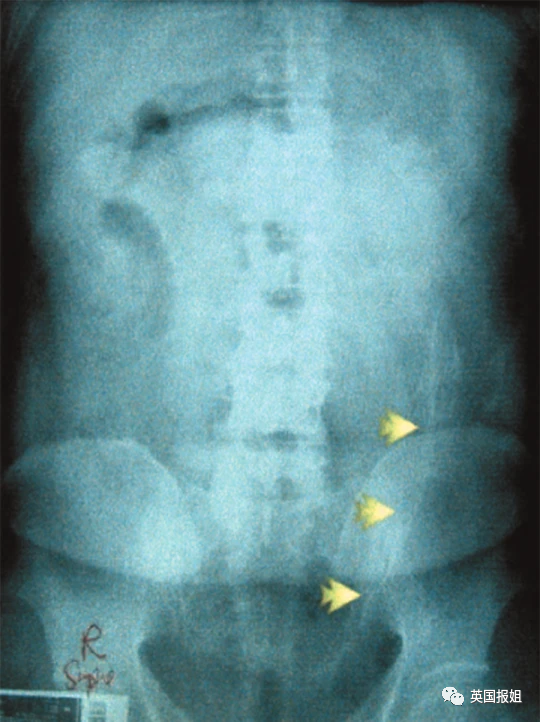

去年,英国医生卡罗尔·库珀在社交网站上很火。因为她收治的病人,菊花里卡的东西实在太大胆了。

她告诉记者她从医这么多年,直肠里卡什么东西都见过,比如15个煮熟去皮的鸡蛋之类的,但没有一个比得上这次出诊。

一名军迷男子下体塞入了一枚17cmX6cm的二战时期反坦克炮弹,当然,他说是滑倒造成的。

医生非常慌,就算她医术再高明,也是没有进行过军械拆卸的,于是她职业生涯中第一次报警叫来了拆弹部队。

经过了拆弹部队和医院多个诊室的会诊,终于判定炮弹已没有引爆危险,在复杂的手术后将其取出。